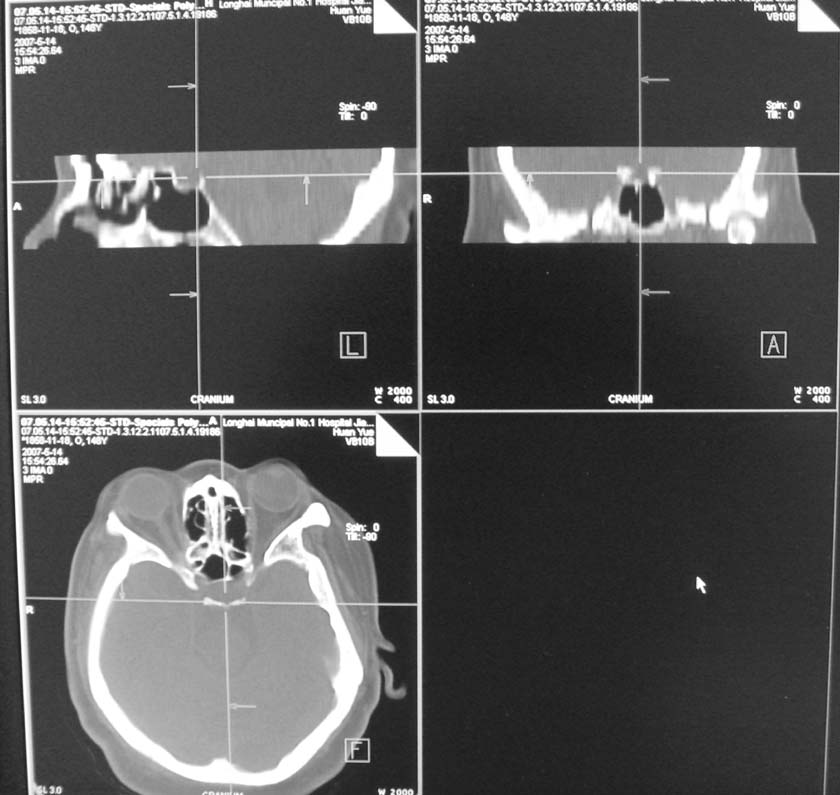

以下是引用天南地北在2007-5-15 23:30:00的发言:[br]看不出来什么[br]建议冠面增强扫描,或mri检查

以下是引用郭凯在2007-5-16 0:17:00的发言:[br]看不到,如果临床支持的话还是做mri看一下吧,对垂体微腺瘤比较敏感.[br]ct上看不到不能乱报.

以下是引用jiangjing在2007-5-16 11:06:00的发言:[br]看不出来什么[br]建议冠面增强扫描,或mri检查